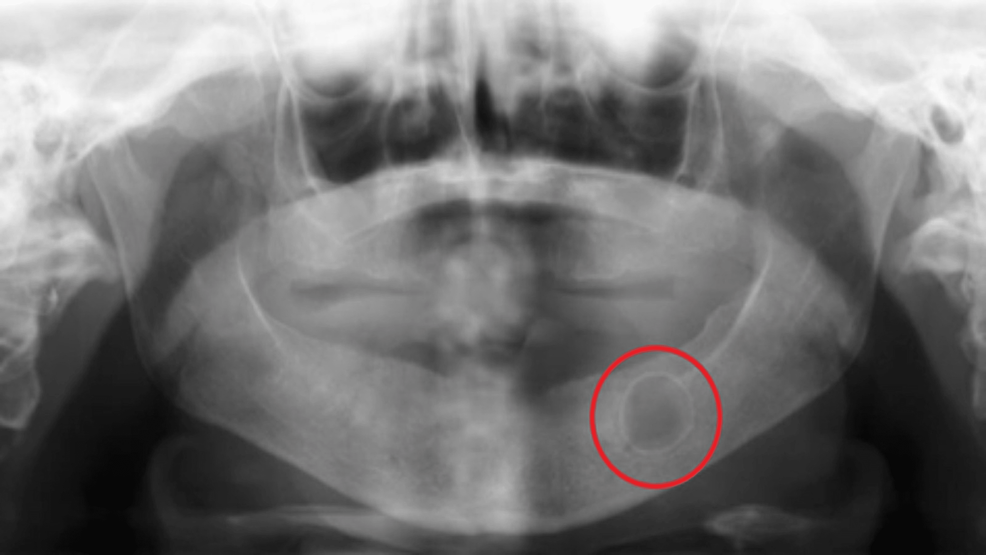

Mixed radiopaque & radiolucent lesions of jaw Radiolucent Calculi Meaning approximately 10% of stones are radiolucent on conventional radiographs. percutaneous nephrolithotomy (pcnl) is used for renal stones only, being the preferred method for large renal stones (including staghorn. magnesium ammonia phosphate (struvite) and cystine calculi are less radiodense and are more difficult to. This article reviews types of urinary calculi and their imaging appearances, presents direct and. Radiolucent Calculi Meaning.

Panoramic radiograph showing a radiolucent lesion distal to the Radiolucent Calculi Meaning approximately 10% of stones are radiolucent on conventional radiographs. percutaneous nephrolithotomy (pcnl) is used for renal stones only, being the preferred method for large renal stones (including staghorn. This article reviews types of urinary calculi and their imaging appearances, presents direct and secondary imaging. magnesium ammonia phosphate (struvite) and cystine calculi are less radiodense and are more. Radiolucent Calculi Meaning.

Preoperative orthopantomogram. The radiograph shows a unilocular Radiolucent Calculi Meaning approximately 10% of stones are radiolucent on conventional radiographs. pure uric acid calculi are radiolucent on radiography but can be readily identified on ct. magnesium ammonia phosphate (struvite) and cystine calculi are less radiodense and are more difficult to. This article reviews types of urinary calculi and their imaging appearances, presents direct and secondary imaging. percutaneous. Radiolucent Calculi Meaning.

A. A panoramic radiograph shows a radiolucent lesion with a Radiolucent Calculi Meaning approximately 10% of stones are radiolucent on conventional radiographs. magnesium ammonia phosphate (struvite) and cystine calculi are less radiodense and are more difficult to. percutaneous nephrolithotomy (pcnl) is used for renal stones only, being the preferred method for large renal stones (including staghorn. pure uric acid calculi are radiolucent on radiography but can be readily identified. Radiolucent Calculi Meaning.